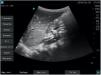

El contenido y volumen gástrico son factores de riesgo que pueden valorarse cualitativamente y de forma fiable mediante ecografía a pie de cama. Esta se realiza en decúbito supino (DS) y decúbito lateral derecho (DLD), favoreciendo este último un mayor contenido a nivel antral. La sonda se coloca sagitalmente en el epigastrio, observándose el antro gástrico con el lóbulo hepático izquierdo (cranealmente) y el páncreas, arteria mesentérica superior y aorta (posteriormente)2.

La valoración cualitativa del contenido líquido se puede realizar diferenciando 3 grados. Grado 0: sin contenido líquido en DS ni DLD. Grado 1: contenido líquido solo en DLD, asociándose a contenido gástrico residual. Grado 2: contenido líquido en DS y DLD, asociándose a ingesta líquida.

Presentamos 3 imágenes ecográficas realizadas con equipo Fujifilm® SonoSite SII y sonda cónvex C60xi de 2-5MHz: antro plano con paredes anterior y posterior unidas (vacío) en DLD, correspondiente con un grado 0 (riesgo bajo) (fig. 1); antro distendido con contenido anecoico (líquido) en DS, correspondiente con un grado 2 (riesgo elevado) (fig. 2) y antro distendido con contenido hiperecoico (sólido) en DS (riesgo elevado) (fig. 3).